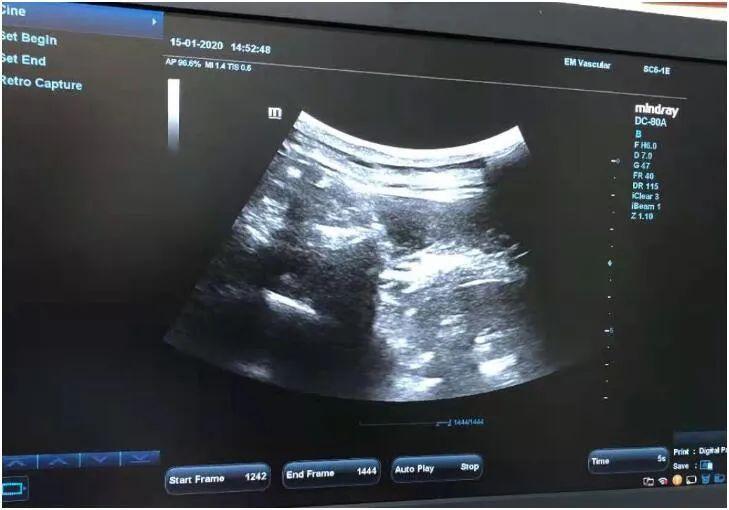

超声引导下神经根阻滞

神经阻滞是急性带状疱疹性神经痛最好的治疗方法,具有迅速镇痛、改善局部血液循环、促进愈合、预防发生带状疱疹后遗神经痛等有点。